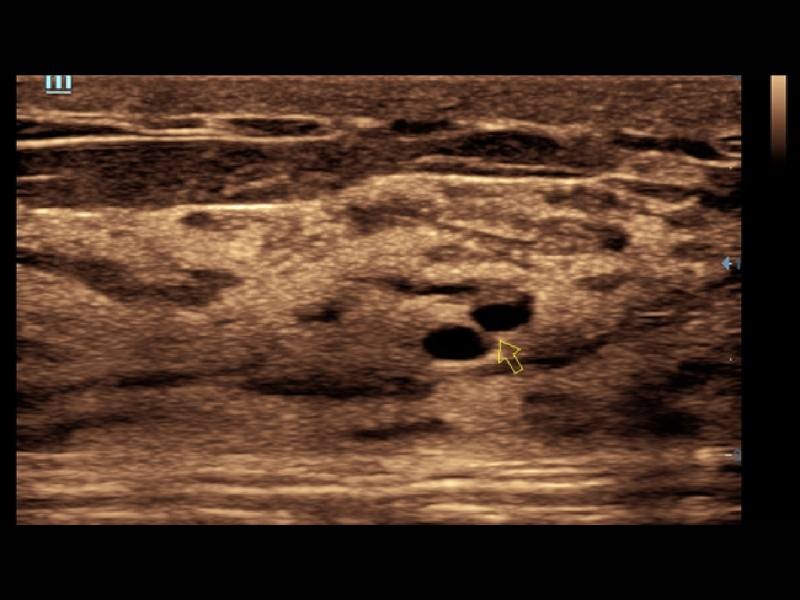

O Smart Track proporciona uma otimização rápida e inteligente das imagens vasculares com apenas um toque. Ele pode otimizar o espectro de cor, energia e PW por meio de rastreamento automático e reduz as etapas demoradas. Portanto, o fluxo de trabalho do exame vascular é simplificado por meio de uma visão ideal.